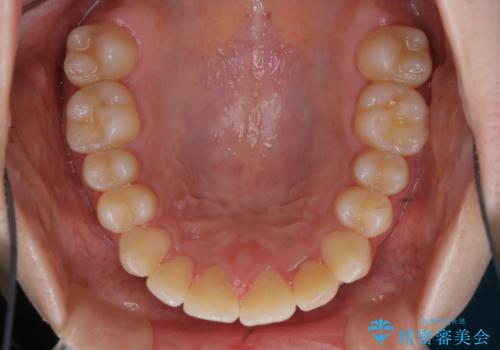

矯正治療終了後にPMTC(Professional Mechanical Tooth Cleaning)

- 矯正治療が終了したため、クリーニングでもきれいにしたいとのことでした。PMTC60分コースを行いました。

矯正治療やセラミックなどによる被せ物の治療終了のタイミングではクリーニングを行い、汚れや着色の除去、歯と歯の間・歯と歯肉との境目などのケアをしっかりすることをおすすめしています。

ご自身での歯ブラシ・セルフケアを行うと同時に、定期的なクリーニング(PMTC)を行うことで、いつまでも健康な歯を保つことができます。